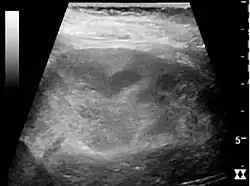

Figure 15. End-stage hydronephrosis with cortical thinning. Measurement of pelvic dilatation on the US image is illustrated by '+' and a dashed line.[1]

Figure 16. Hydronephrosis with dilated anechoic pelvis and calyces, along with cortical atrophy. The width of a calyx is measured on the US image in the longitudinal scan plane, and illustrated by '+' and a dashed line.[1]

Figure 17. Same patient as in Figure 16 with measurement of the pelvis dilation in the transverse scan plane illustrated on the US image with '+' and a dashed line.[1]